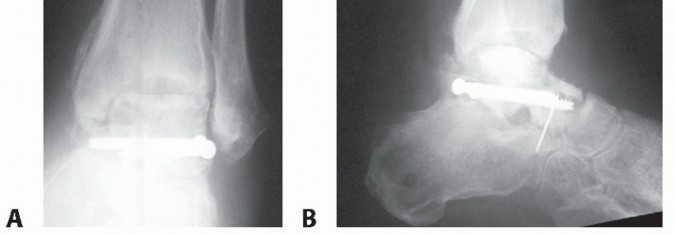

- The arthrodesis must be in a plantar neutral position. A fusion with the foot in equinus will severely compromise the functional outcome (FIG 4).

- FIG 4 • A. Tibiocalcaneal arthrodesis with loss of talar head and navicular in crush injury of foot. B. Full lateral x-ray of tibia and foot is accurate method to evaluate foot position. With no ankle motion and compromised forefoot motion, aligning the foot in plantar neutral position and correct forefoot rotation is

essential for a functional result. Observe mature proximal bone transport to equalize leg length.